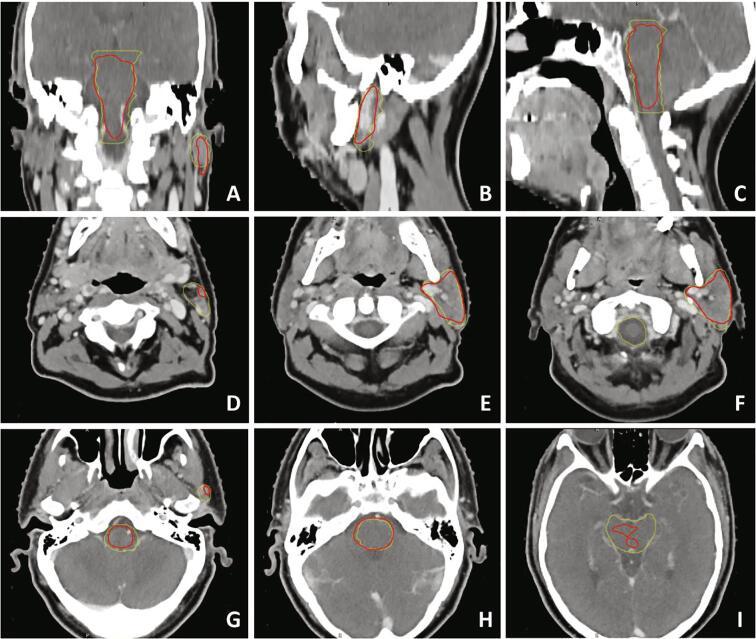

The CT-based DLC model, trained at the University Medical Center Groningen (UMCG), was applied to an independent set of 58 patients from the Radboud University Medical Center (RUMC). DLC results were compared to the RUMC manual reference using the Dice similarity coefficient (DSC) and 95th percentile of Hausdorff distance (HD95). Craniocaudal spatial information was added by calculating binned measures. In addition, a qualitative evaluation compared the acceptance of manual and DLC contours in both groups of observers.

Good correspondence was shown for the mandible (DSC 0.90; HD95 3.6 mm). Performance was reasonable for the glandular OARs, brainstem and oral cavity (DSC 0.78-0.85, HD95 3.7-7.3 mm). The other aerodigestive tract OARs showed only moderate agreement (DSC 0.53-0.65, HD95 around 9 mm). The binned measures displayed the largest deviations caudally and/or cranially.

下颌骨显示出良好的一致性(DSC 0.90;HD95 3.6 mm)。腺体危及器官、脑干和口腔的性能较为合理(DSC 0.78 - 0.85,HD95 3.7 - 7.3 mm)。其他消化道呼吸道危及器官仅显示出中等程度的一致性(DSC 0.53 - 0.65,HD95约为9 mm)。分组测量值在尾部和/或头部显示出最大偏差。